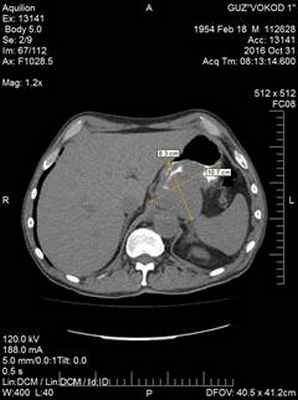

31.10.2017. Компьютерная томография с контрастным усиление «Ultravist»: опухоль верхнего этажа брюшной полости 8,3х10,7х13,7 см, исходящая из стенки желудка – ГИСТО (Рис. 1).

Рис. 1. Компьютерная томограмма пациента С